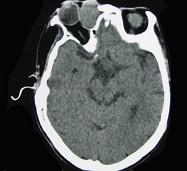

问题 女性,40岁,右眼反复溢泪伴眼球渐进性突出2年余,眼球运动受限,CT检查如图所示,请选择最可能 ( )

选项 A、泪囊血肿 B、眶内结核 C、泪囊囊肿 D、泪腺血肿 E、泪腺囊肿

答案 C